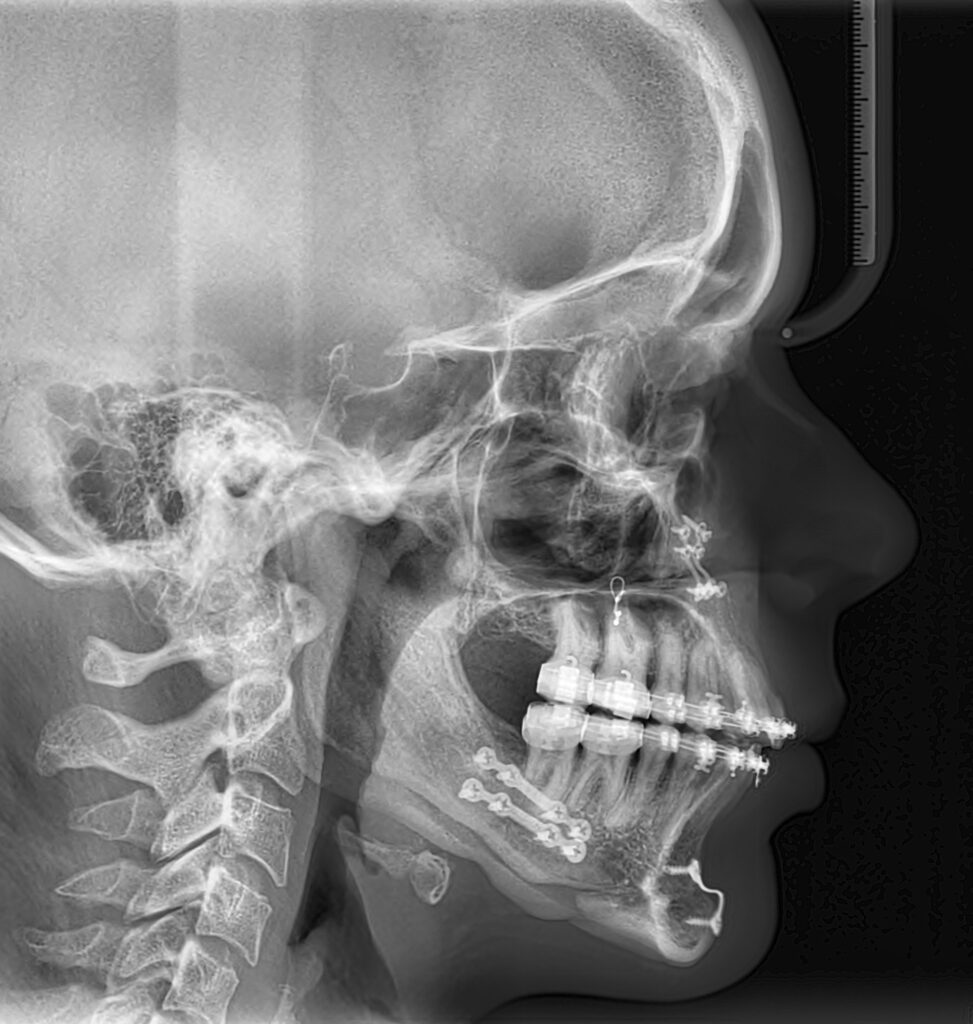

Een te grote onderkaak wordt naar achteren verplaatst door een verticale botsnede te maken in de onderkaak. Hierna wordt het deel waar het kaakkopje aan vast zit een beetje naar buiten gehouden. Dan kan de onderkaak naar achteren worden geplaatst waardoor de bot-stukken elkaar gedeeltelijk overlappen. Er wordt dus geen stukje bot uitgehaald. Deze methode kan “via de mond” worden uitgevoerd waardoor uitwendig geen litteken achterblijft. Het komt vrijwel niet meer voor dat na deze ingreep de boven- en onderkaak aan elkaar bevestigd hoeven te worden met staaldraadjes. In verreweg de meeste gevallen worden alleen elastiekjes aan de ‘slotjes’-beugel gebruikt om na de operatie de kaken in de juiste positie ten opzichte van elkaar te houden. Het bot zelf wordt tijdens de operatie met kleine titanium schroefjes en plaatjes aan elkaar geschroefd. De mond kan dus meestal meteen na de operatie weer worden geopend.

De duur van de opname in het ziekenhuis varieert meestal van twee tot drie dagen. Tijdens deze dagen worden controlefoto’s gemaakt.